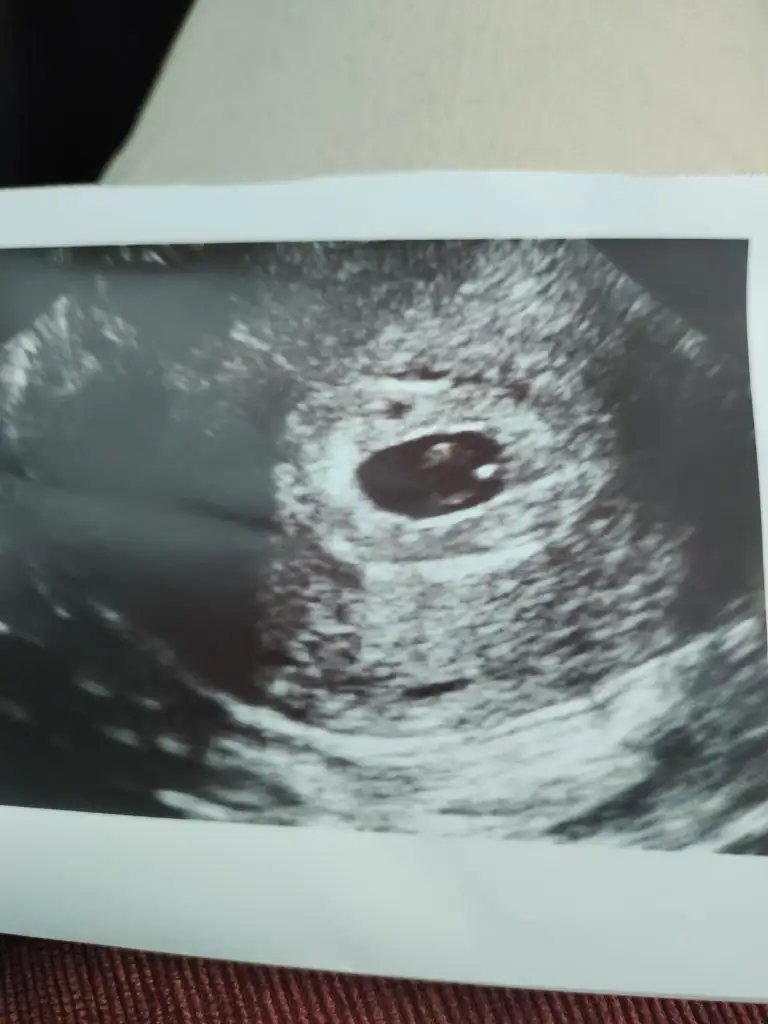

Canım ben ilk bebeğim de ilk muayenede vajinal olmuştum bir sorun yaşamadım göremeyip stres olmaktansa kendim diyordum hocam direk vajinal bakalım diye en azından ilk haftalar daha net görünüyor du bak bu foto ilk muayenede çekilmişti oğlumda 5 kusurlu haftaydi sanırsamKızlar vajinal sizce ilk dönemde sıkıntı mı ne düşünüyorsunuz